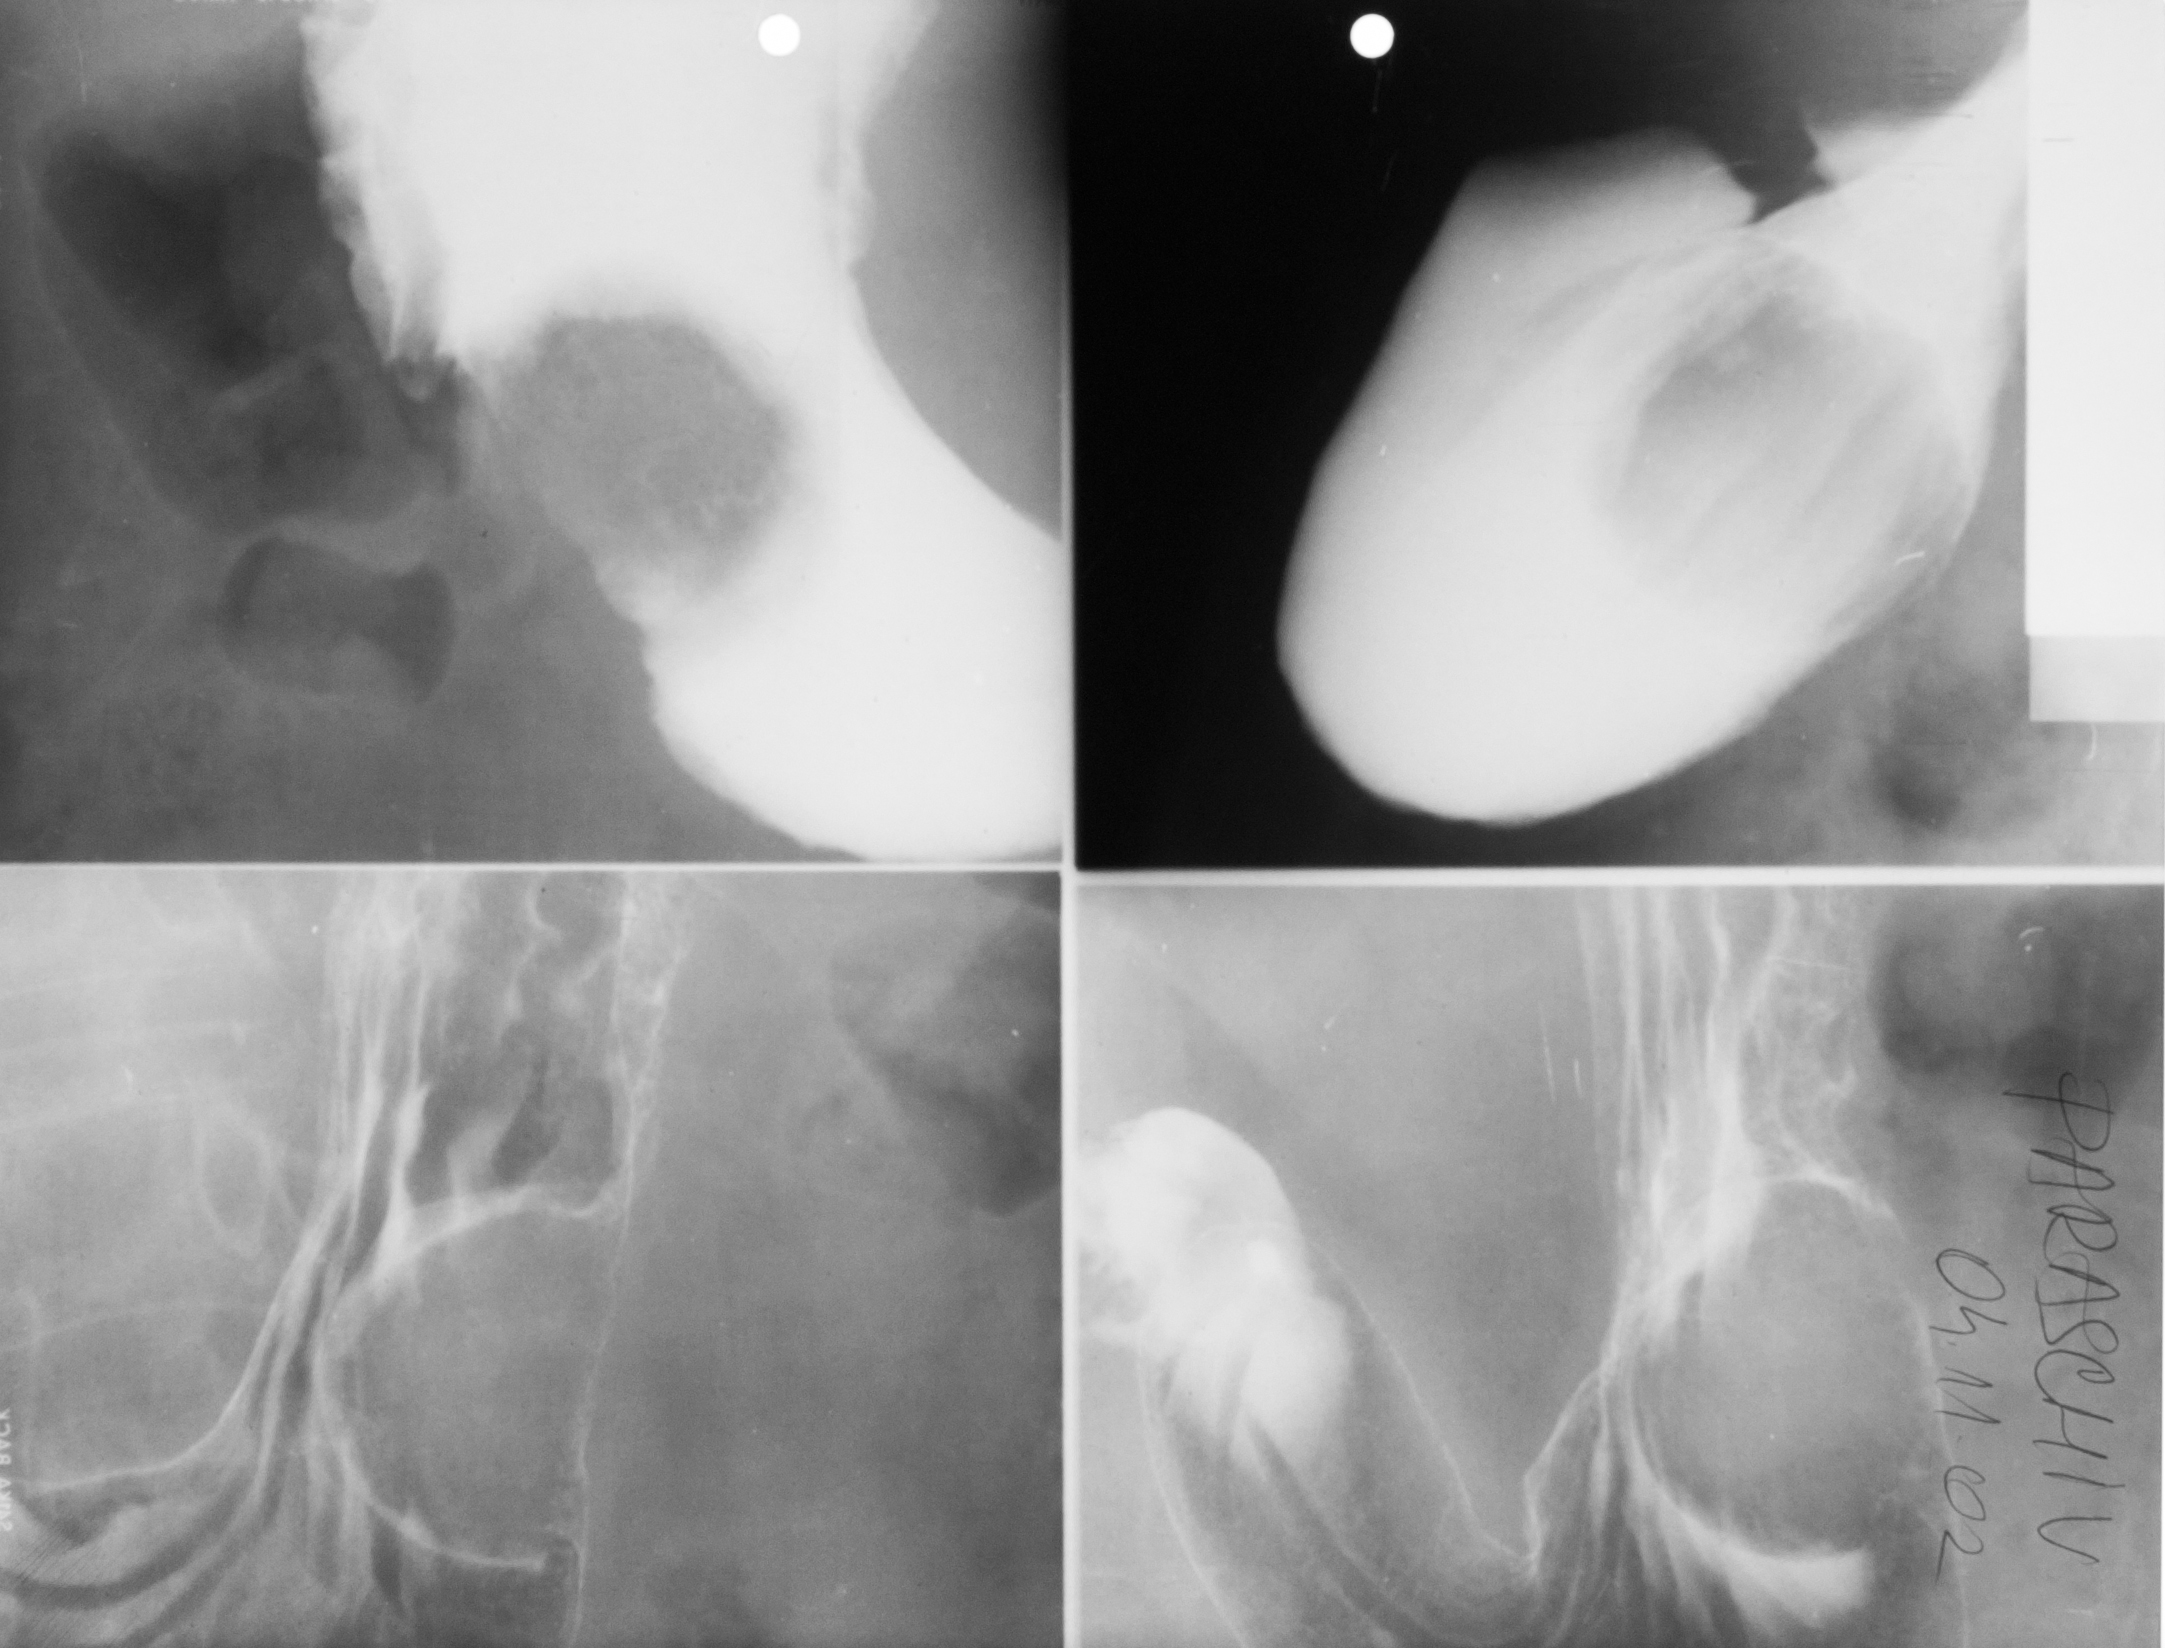

:IMAGINE NORMALA

Urografie cu substanta de contract intravenous, efectuata la 9 minute postinjectare, in care se observa ariile renale, de dimensiuni normale, nefrograma si opacifierea aparatului pielocalicial care este de dimensiuni normale, uretere la nivelul vezicii urinare

DUBLICITATE PIELOCALICIALA STANGA

Urografie la aproximativ 15 minute, se vede ca in partea dreapta este aparat pielocalicial de aspect normal, ar in partea stanga sunt 2 aparate pielocaliciale, undeva de la calicele superior, nu s-a produs unirea si are un ureter mai mic care se uneste cu ureterul principal

HIDRONEFROZA

Urografie la 25 minute, in partea stanga hidronefroza, distensia pielocaliciala, in partea dreapta aspect radiologic normal. Atat calicele cat si bazinetul sunt dilatate in partea stanga.

HIDRONEFROZA RINICHIULUI DREPT

URETEROHIDRONEFROZA

In partea stanga, expunere tardiv la 60 min dupa injectare. In partea dreapta nu este parenchim renal, este vorba despre rinichi unic.

HIDRONEFROZĂ MARCATĂ STÂNGĂ

SINOSTOZA

Radiografie de mana, falangele de la degetele 3 si 4 sunt sudate ceea ce inseamna sinostoza, cu consecinta sindactilie

FOCOMELIE

Hipoplazie ulnara, agenezie de radius

SCOLIOSTOZA DE RADIUS STANGA, HIPOPLAZIE ULNARA STANGA, AGENEZIA OASELOR CARPIENE DREAPTA

BLOC VERTEBRAL CONGENITAL CERVICAL

Format din trei corpuri vertebrale, care are inaltime egala cu suma inaltimilor corpurilor vertebrale.

PINTENI CALCANEENI DORSAL SI PLANTAR

Se observa calcifieri a insertiilor ligamentare la nivelul tuberozitatii calcaneene

OSTEOLIZA

Radiografie de bazin cu arie de osteoliza, bine delimitata rotunda, net liniar delimitata, care nu modifica, nu sparge conturul osos

Leziunea elementară este osteoliza

SCLEROZA ENDOSTALA

Radiografie de gamba, profil, cu proces de endoscleroza la nivelul treimii superioare a diafizei, cu ingustarea neregulata a canalului medular

SPONGIOSCLEROZA

Scleroza la nivelul corpurilor vertebrale, sunt mai albe, mai dense. In corpurile vertebrale avem tesut osos spongios(de asta se numeste spongioscleroză)

OSTEOPOROZA

Radiografie unui bont de amputatie, cu zona de scaderea intensitatii osului, o transparenta a osului in regiunea epifizelor tibiei si femurului, cu trabecule mai subtiri, compacta diafizara ingustata

Osteoporoza pătată

Transparenta oaselor carpiene,neuniform, cu aspect pătat, trabecule fine, densitatea osului scazuta,dar neuniform, caracteristica de obicei proceselor acute (de exemplu politraumatism)

Cifoza rotunda, caracteristica persoanelor in varsta, datorata osteoporozei generalizate

- radiografie de coloana toracala, cu accentuarea cifozei toracale

- corpuri vertebrale mai putin opace decat ar trebui si avand forma trapezoidala, nu dreptunghiulara, cu tasare anterioara a acestor corpuri vertebrale

Osteomiolita cu sechestru

Radiografie de femur, undeva la nivelul diafizei, arie de osteoliza cu mic sechestru osos cu zona de osteoporoza in vecinatate si cu reactie periostala

Hiperostoza tibiei, care e de dimensiuni mari, fara canal medular, deci cu proces de scleroza endostala si cu ingrosarea semnificativa undeva in treimea superioara si mijlocie a diafizei, ca si consecinta a osteomielitelor cronice

PANARIȚIUL(este o osteită)

Osteoliză marginală la nivelul falangei distale,cu parți moi tumefiate,cu delimitare de fragment osos.

PANARIȚIU

Tumefacție de părți moi,liză marginală cu delimitarea unui fragment osos

OSTEITĂ LA NIVELUL UNUI BONT DE AMPUTAȚIE

Arie de osteoliză marginală,care delimitează și detașează un fragment osos distal

TUBERCULOZA GENUNCHIULUI

Radiografie de genunchi (Rx.de fata)

Nu se vede niciun spatiu articular, lipseste total

Suprafetele articulare sunt neregulate si sunt punti osoase ce trec dintr-o parte in cealalta,deci e o anchiloza radiologica, datorata osteoartritei (cu distrugerea atat a tesutului cartilaginos, cat si a osului spongios de dedesubt)

TUBERCULOZA GENUNCHIULUI

RX de profil

Osteoartrita TBC la nivelul coloanei vertebrale

Radiografie de coloana toracala, se vad 2 corpuri vertebrale cu spatial dintre ele absent, ele de dimensiuni mai reduse decat normal cu suprafete articulare neregulate, iar adiacent opacitate fusiforma

!!! Se cheama: Morbul lui Bot, (umflatura de pe margine e fusul Botic)

OSTEOARTRITĂ TBC

Accentuarea cifozei dorsale, nu e rotunda ci unghiulara, datorata distructiei unor corpuri vertebrale (lizei acestora), ramanând niste resturi care s-au sudat partial si au facut un bloc vertebral botic

CIFOZĂ ÎN URMA TUBERCULOZEI VERTEBRALE

Osteoporoza in bandă, care e stadiul incipient (stadiul I) de poliartrită reumatoidă

Radiografie comparativa de maini, in care se vede o transparenta crescuta a extremitatilor metacarpienilor (adica a capetelor metacarpienilor, respectiv a bazelor falangelor)

Stadiul II spre III de poliartrita reumatoida

Radiografie comparativa de maini, cu osteoporoza accentuata, cu spatii disparute la nivelul oaselor carpiene si lize semnificative la nivelul spatiilor articulare interfalagiene proximale (deci bazele falangelor, respectiv capetele falangelor proximale), lize marginale cu disparitie de spatii articulare – stadiul 2 spre 3 de poliartrita reumatoida

MODIFICĂRI DE STADIUL 3 DE POLIARTRITĂ REUMATOIDĂ

Osteoporoză accentuată,absenta spațiilor articulare și distrucția severă ale oaselor carpiene,lize,osteolize și subluxații ale falangelor una pe cealaltă cu derivație pe cubitus(derivație cubitală)